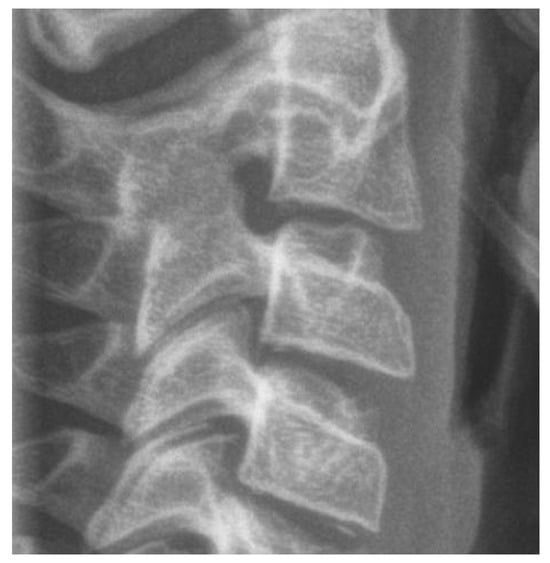

- Skeletal age is commonly assessed using cervical vertebrae and hand–wrist radiographs. Alternative approaches, including metal implants, biochemical markers, and electromyography, have been implemented.

3.3.2. Cervical Vertebrae Radiography

| CVM | cervical vertebral maturation |